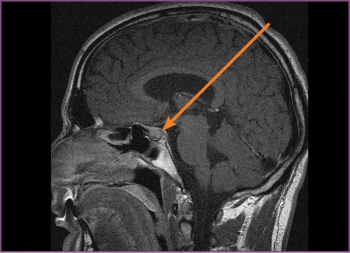

However, despite AZ’s normalised prolactin, his headaches persisted, hence an MRI of the brain, T1-weighted, was ordered. The MRI revealed a macroadenoma in the pituitary fossa, which extended into the suprasellar region compressing the chiasma, there was also dilatation of the third and lateral ventricles suggesting some degree of compression at the aqua duct (see Figure 1). AZ was discharged from the psychiatric unit on aripiprazole to follow up with the endocrinologist, who prescribed cabergoline 0.25mg twice weekly.

Figure 1: Pre-surgery, the first MRI, T1-weighted (sagittal) – the pituitary fossa shows a macroadenoma (11 mm)(click to enlarge)